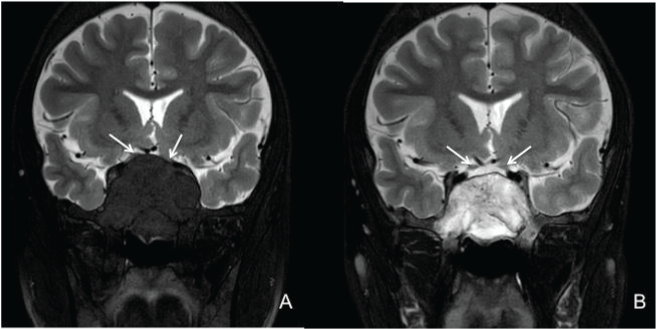

| Figure 3: MRI of the orbit and brain. (A) Coronal T2-weighted showing compression and stretching of bilateral prechiasmatic optic nerves (arrows). (B) Coronal T2-weighted showing reduction in the size of the tumor-like expansion along with improvement of compression and stretching of bilateral prechiasmatic optic nerves (arrows). |